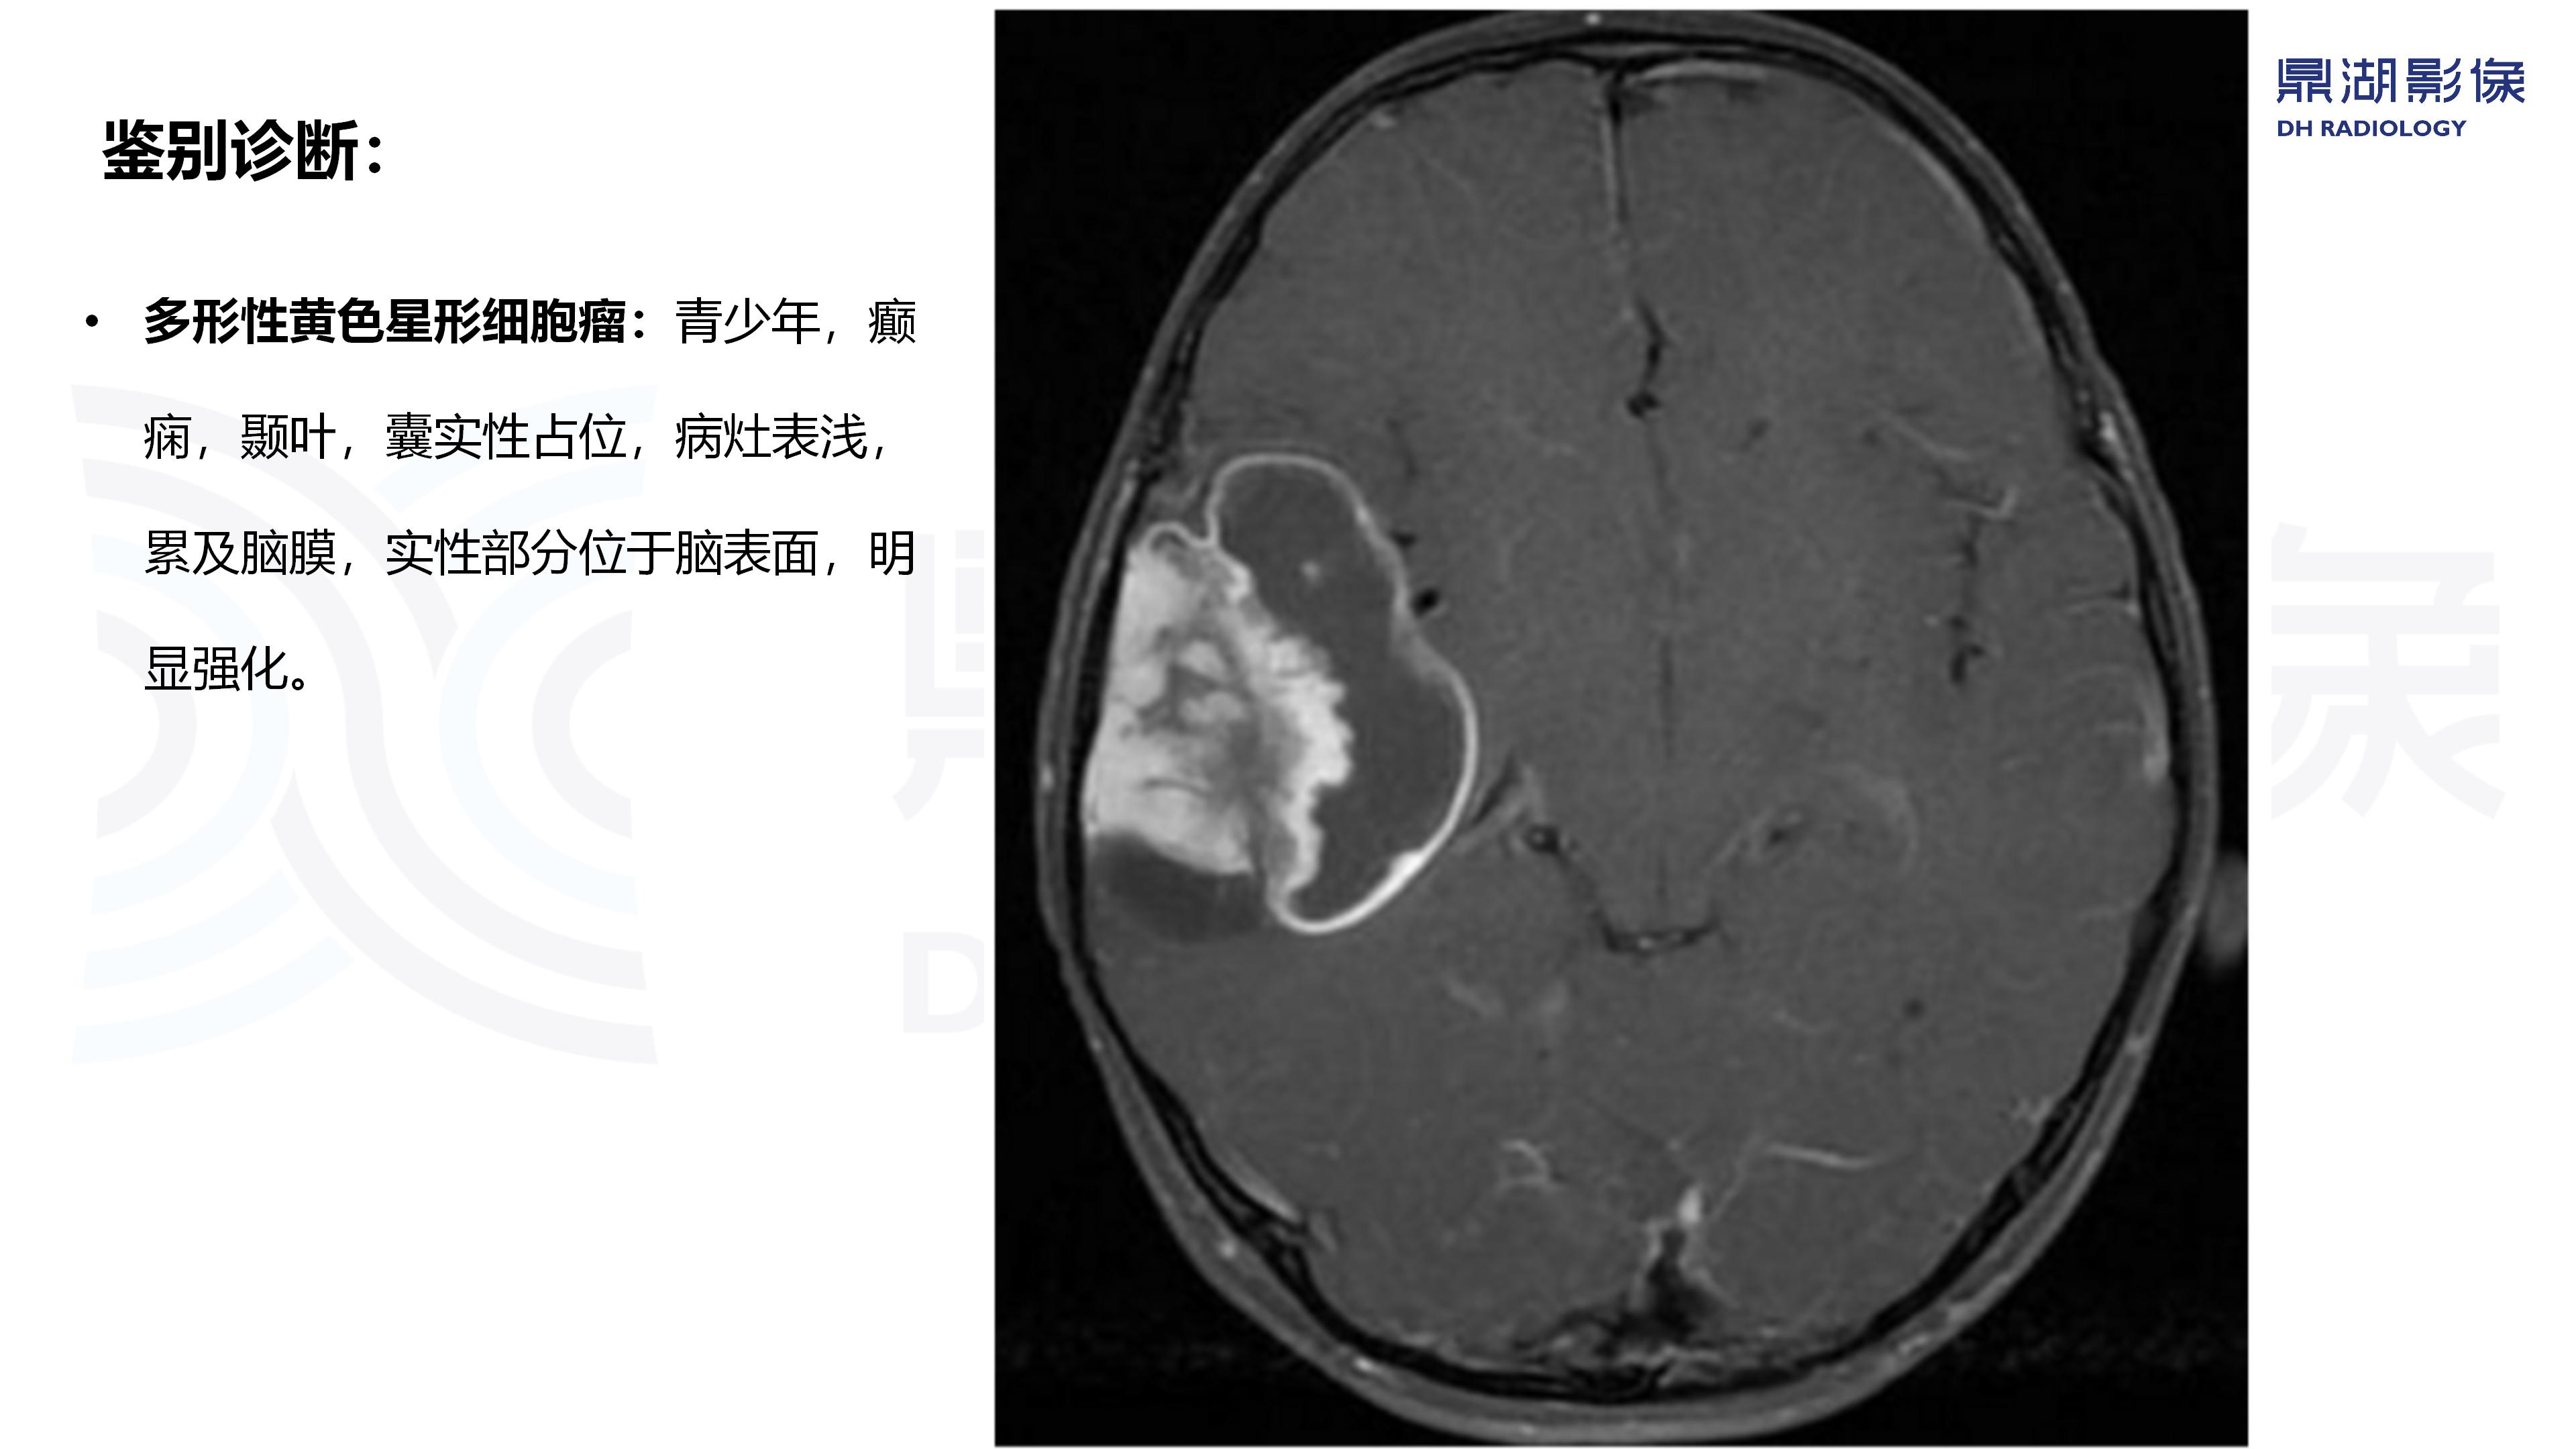

病例分析